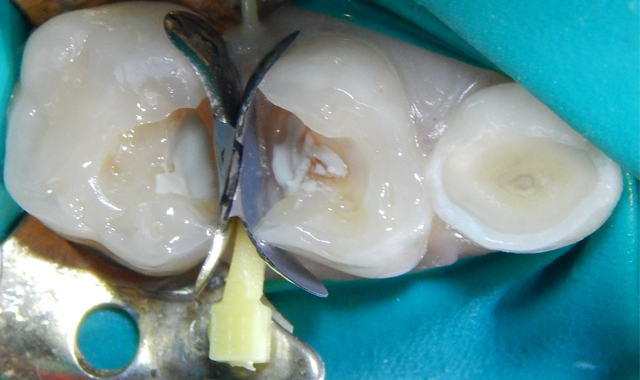

Fig. 2 Fig. 3

Upon the operative visit he remained very cooperative. Single Tooth Anesthesia® (Milestone Scientific) was utilized for local anesthesia and a rubber dam placed (Fig. 2). Removal of the previous restorations was quick, as they demonstrated no evidence of bond with tooth structure. Gross caries was present under the restorations along with obvious micro-leakage staining (Fig. 3).